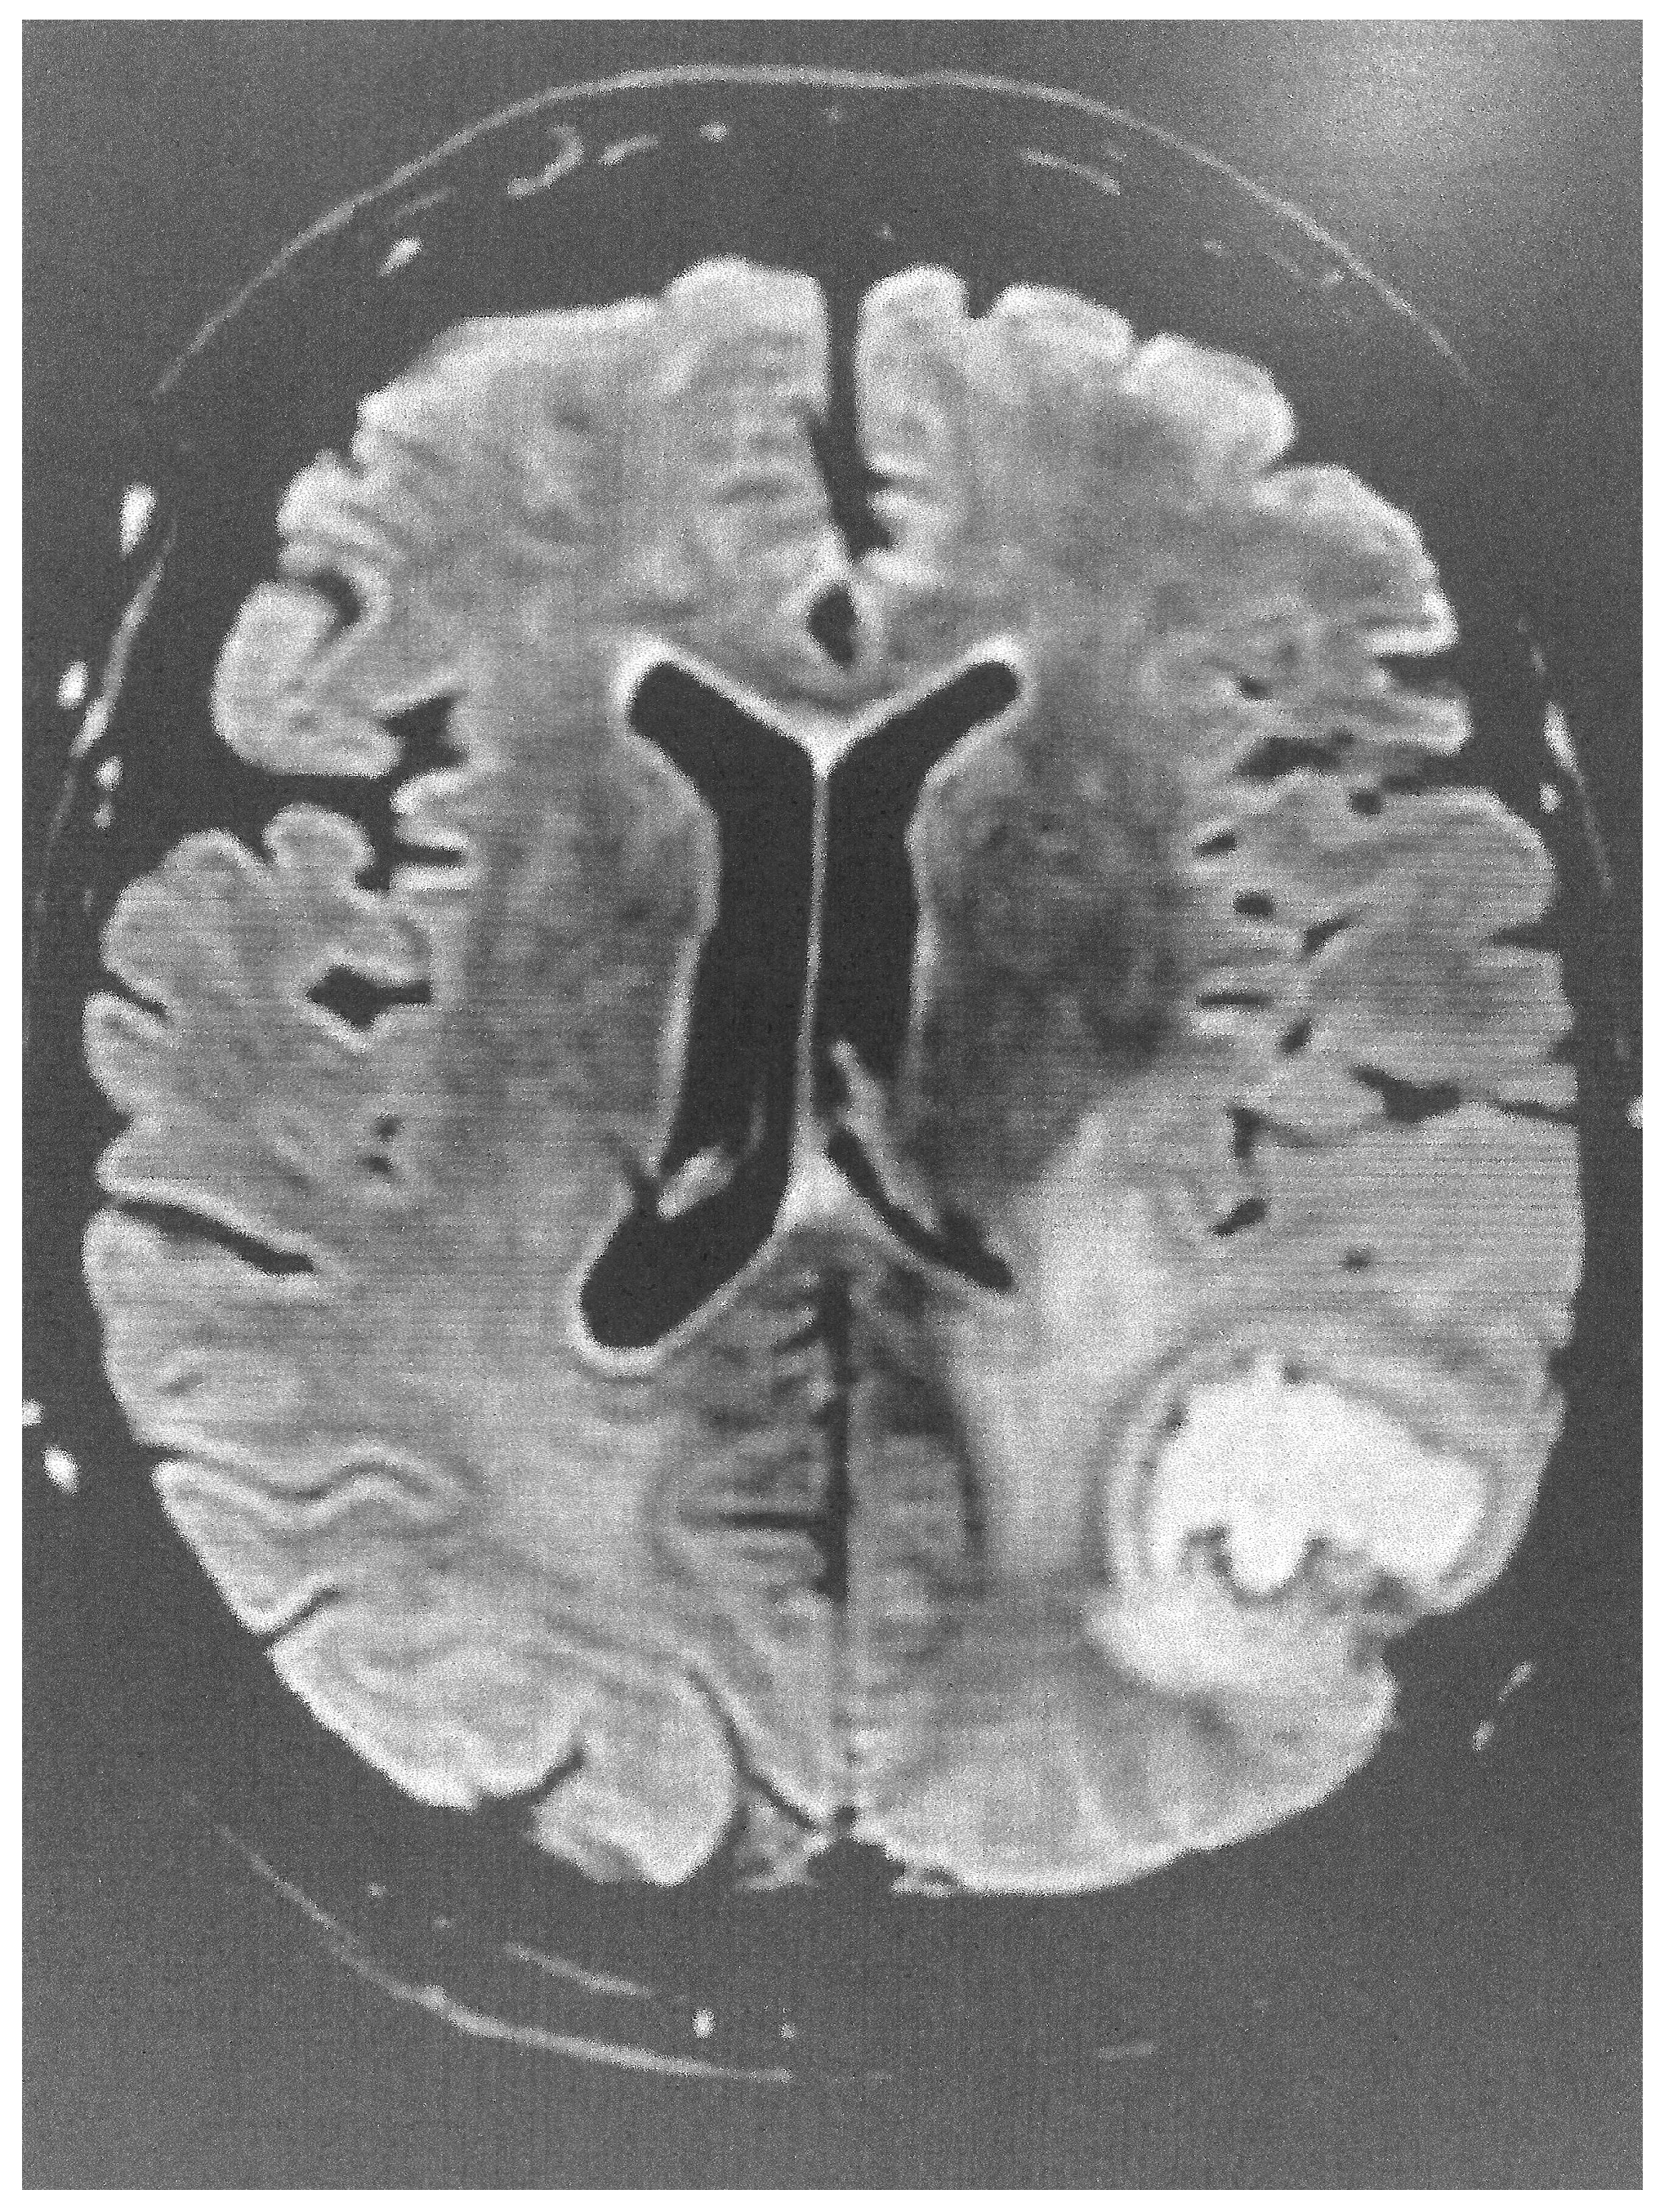

CMR can visualize the typical regional wall motion abnormalities characteristic of TTS, such as apical or mid-ventricular ballooning. In addition, it can detect the presence of myocardial oedema and fibrosis (tissue characterization). The presence of oedema in the absence of positive late gadolinium enhancement (LGE), which represents replacement fibrosis, is typical of TTS. However, positive LGE can be found in patients with a mild cardiac enzyme elevation [3]. CMR may facilitate the differential diagnosis of other cardiac conditions, such as myocardial infarction, myocarditis, and ischemic and non-ischemic cardiomyopathies.

During the acute phase of TTS, CMR is recommended in doubtful cases, especially in those where different therapeutic protocols are needed, as in MINOCA or myocarditis. Furthermore, in the post-acute TTS phase, it is recommended in all patients within 2 months, if they have persisting ECG and/or regional wall motion abnormalities in the echocardiographic evaluation, in order to finally document the diagnosis of TTS [32]. CMR images of TTS are presented in Figure 3 and Figure 4.

Figure 3. Short axis STIRT2 image showing extensive oedema in a patient with TTS.